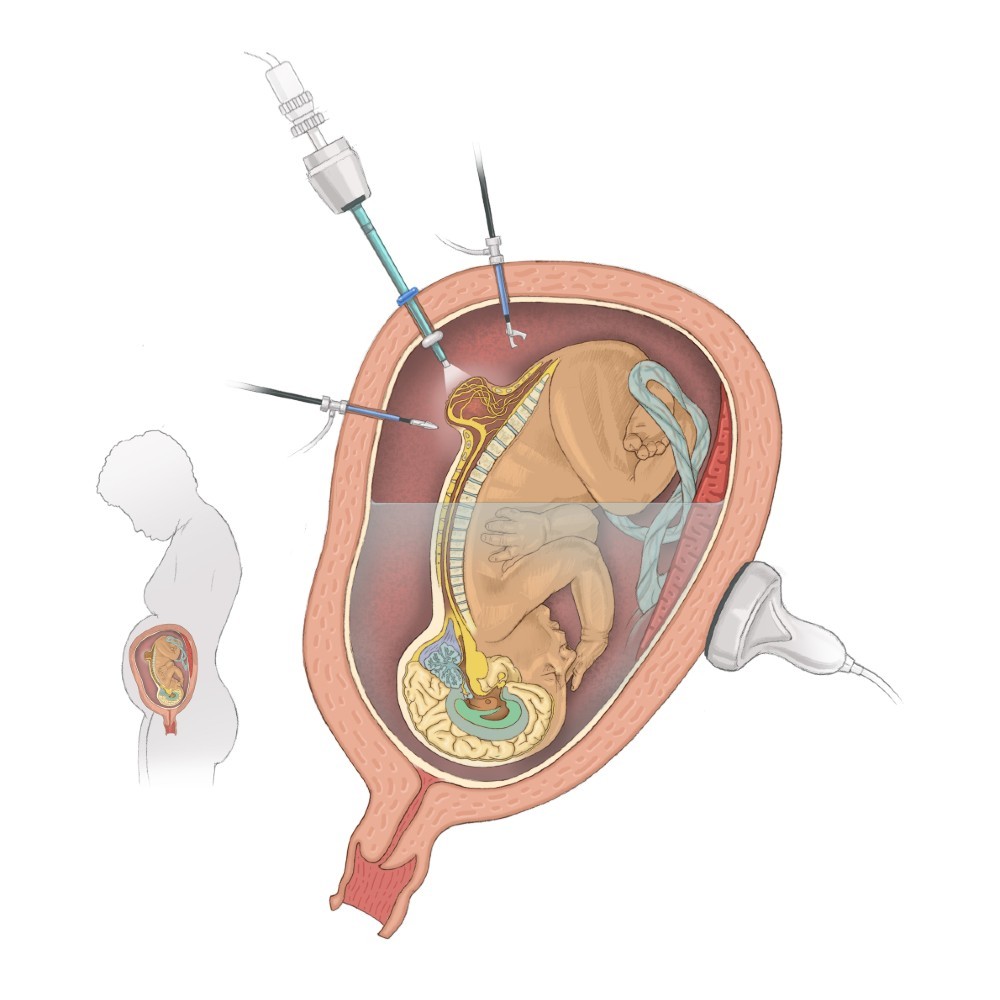

“Our primary outcome measure for the study is successful surgical closure of the spina bifida defect with a watertight patch that approximates native tissue and allows for the natural growth of the spinal cord,” Dr. Papanna says. “The procedure differs from in-utero repair, which requires a large incision on the uterus and delivery by cesarean section. Instead, we will repair the spina bifida defect in two layers through three small incisions in the uterus using fetoscopes and tiny surgical tools. The first layer will be closed using a NEOX®Cord 1K patch as a meningeal patch placed over the spinal cord, followed by a second layer of primary closure of the skin. Mothers will undergo vaginal delivery, unless there is an obstetrical indication for delivery by C-section.”

The NEOX Cord 1K patch is made of cryopreserved umbilical cord and amniotic membrane. Extensive laboratory and clinical research on an ocular wound surface has shown that placental tissues help manage inflammation in wounds, facilitate cell proliferation and create an environment for tissue regeneration. NEOX Cord 1K has demonstrated consistently high closure rates in real-world experiences.

The study, the first to use a meningeal patch to cover the spina bifida defect, will enroll 15 patients, age 18 and older with a singleton pregnancy, a spina bifida defect of 4 centimeters or less and no preterm birth risk factors. Participants also must meet other study qualifications.